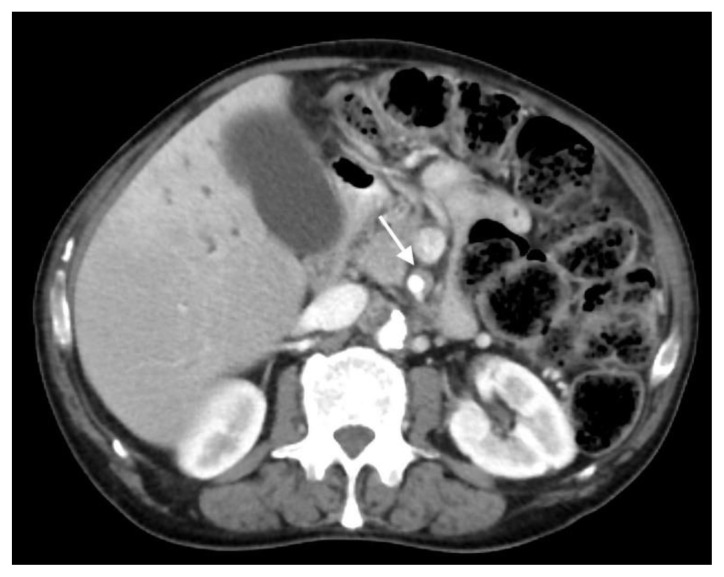

The patient next underwent contrast enhanced computed tomography (CT) of the abdomen and pelvis, which revealed infiltrative soft tissue in the region of the biliary hilum with moderate to severe upstream intrahepatic biliary dilatation, suggestive of a stricture (Figure 1). There was heterogenous enhancement throughout the liver, with a focal hypoenhancing region noted in the left hepatic lobe (Figure 2). It was unclear if this focal lesion represented a hepatic mass, pseudotumor or inflamed parenchyma. The pancreas had lost its normal lobulated architecture and its parenchyma was diffusely enhancing with a surrounding rind of soft tissue (Figure 1). These findings were suggestive of autoimmune pancreatitis. Soft tissue also surrounded the proximal aspects of the superior and inferior mesenteric arteries (Figures 3, 4). Asymmetric prominence of the seminal vesicle was also noted, thought to be due to an underlying prostatic lesion or an infectious or inflammatory prostatitis.

Figure 2.

78 year-old male with IgG4-related autoimmune disease.

Findings: Axial contrast-enhanced CT shows heterogenous hepatic parenchymal enhancement (arrow).

Technique: Axial Multi-detector CT, Portal Venous phase (100 ml Omnipaque), mA 50–200; kV 120; 5.0 mm slice thickness.